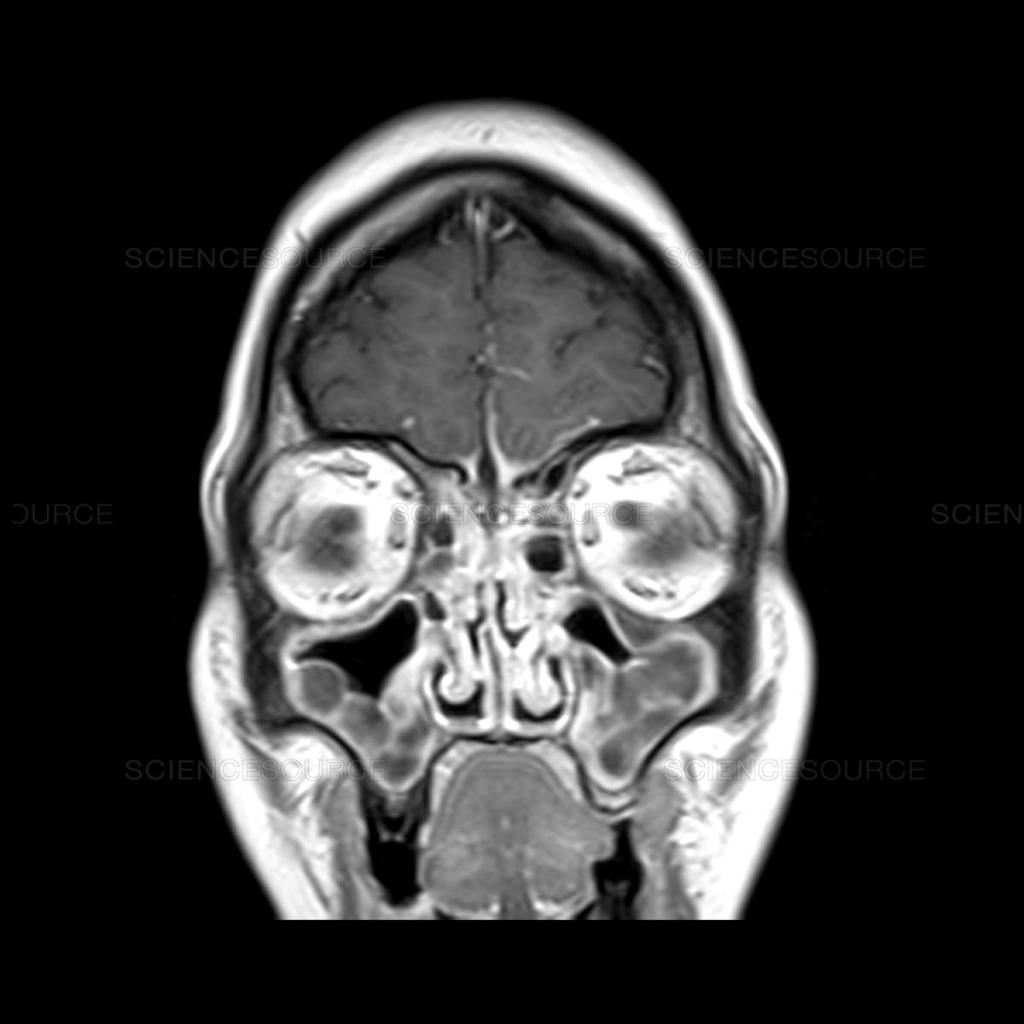

MRI of the head

you can see the turbinates and the sinuses – and the brain!

I was shocked, for several reasons. I took the Cipro, then I told him about Dr J and the polyps. He said “I didn’t see any polyps up there, but let me look again.” and he did. “I still don’t see any polyps.” I had my doubts that he could see anything with a bare light bulb and a mirror. Shouldn’t he be using a fiber optic cam? “you said they took an MRI, do you have it with you?” I did, and gave it to him. He put it up on his screen “Hmmm, where did you say they took this?”. NYU. “This MRI is excellent. They take very good MRI’s at NYU, But I STILL don’t see any polyps.”